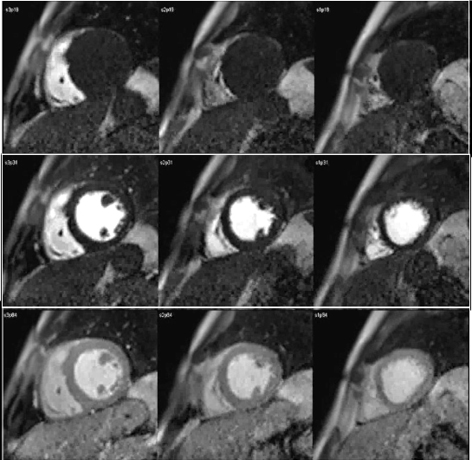

The study of myocardial perfusion by CMR was introduced during the early years of the short history of the technique itself [20], and the approach then proposed has not changed essentially. Here, as in nuclear scans, it is the kinetics of a tracer, an MR contrast agent (CA) which is monitored during its first pass through the heart chambers and, finally, the left ventricular myocardium, that enhances its signal as the agent reaches the microcirculatory network of the heart muscle (Fig. 1).

Fig. 1.CMR sequence of myocardial perfusion. Three simultaneous levels of the left ventricle (LV) are imaged every heart beat for 60 cycles during the first-pass of a contrast agent. Presented here are those frames corresponding to the wash-in of the agent through the right ventricular chamber (top row), then into the left one (middle row), and, finally, through the ventricular myocardium (bottom row), where the perfusion of the heart muscle is visually perceived as a global, homogeneous increase in signal intensity.